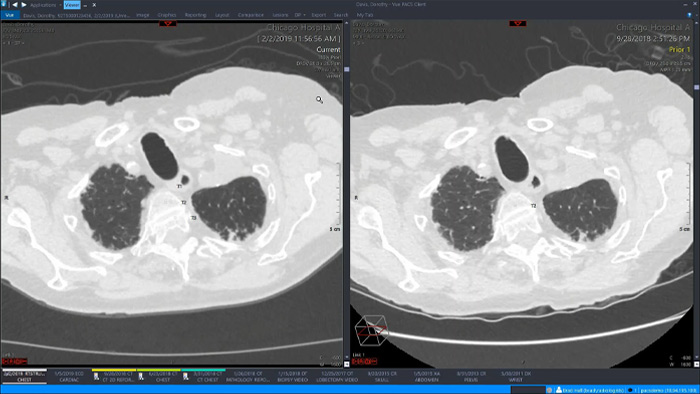

Einige der direkten Vorteile einer einheitlichen Vorgehensweise in Form eines einzelnen umfassenden Arbeitsbereichs für die Radiologie sind die Verfügbarkeit einer integrierten modernen 3D-Nachverarbeitung sowie von Bildverteilungsfunktionen, die sich bequem über eine zusätzliche Betrachtungsregisterkarten aufrufen lassen.

Ein einzelner umfassender Arbeitsbereich, der vollständig in die klinische Bildgebungsplattform und das diagnostische Betrachterprogramm integriert ist, bietet einfachen und effizienten Zugang zu allen erforderlichen Tools der einzelnen klinischen Bereiche und zusätzlich auf einfachen Knopfdruck zu den Tools für die fortschrittliche Visualisierung (beispielsweise CT-Kolonoskopie, 3D-Nachverarbeitung und Spektralbildgebung). Dies führt zu mehr Effizienz bei der Befundung und erhöht die Diagnosesicherheit.

Fortschrittliche Visualisierung mit zuverlässigen Tools für eine KI-gestützte quantitative Beurteilung und automatische Ergebnisausgabe